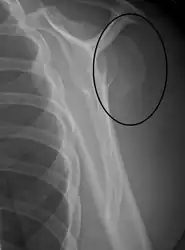

Fracture dislocation of the right shoulder